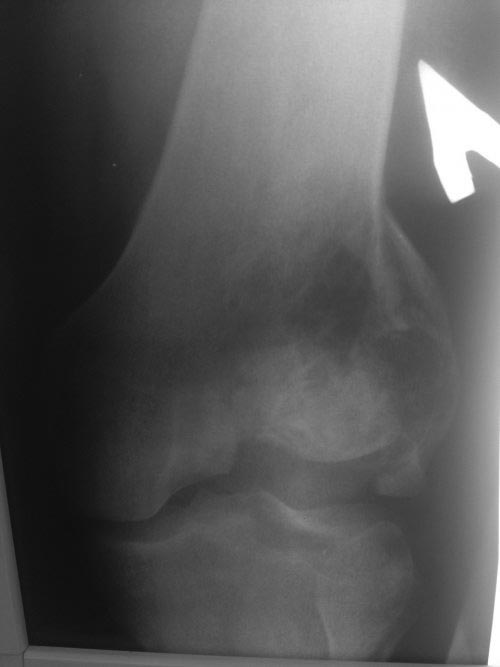

[Ortho] Патологический перелом мыщелка бедра

Рентгеновский снимок